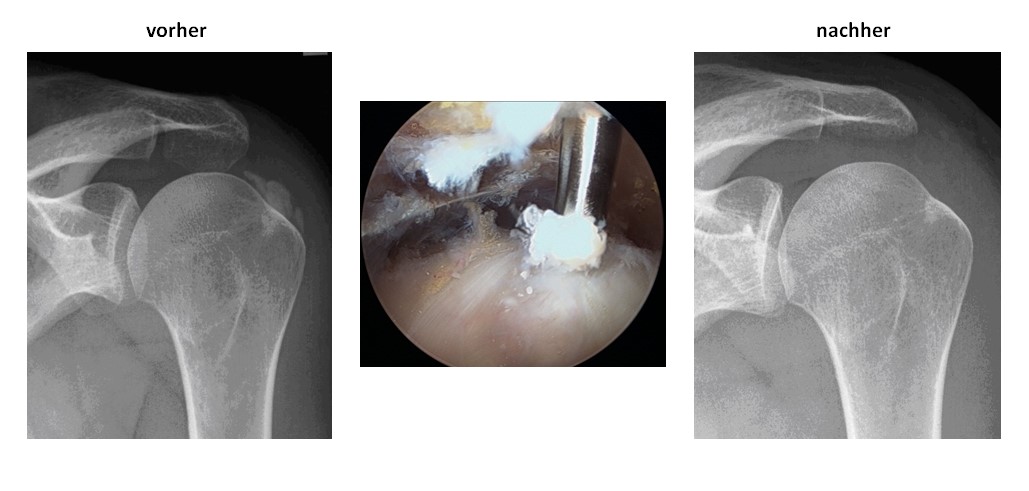

Entfernung von Kalkherden im Bereich der Sehnen (Tendinosis calcarea)

Beispiel - Arthroskopische Entfernung von Kalkherden in der Supraspinatussehne mit Erweiterung des Schulterdaches